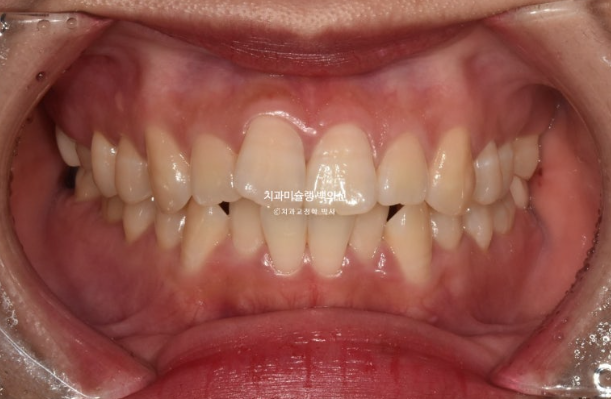

23년 10월 교정을 위해 온 30대 환자분입니다.

앞니는 뻗쳐있고 좌측 큰어금니 자리가 비어있습니다.

아래 앞니는 삐뚤하여 배열할 공간이 필요하고

위 첫번째 큰어금니 (제1대추치)가 한쪽은 발치되어있고 한쪽은 아직 발치는 안 했지만 발치진단이 나온 상황입니다.